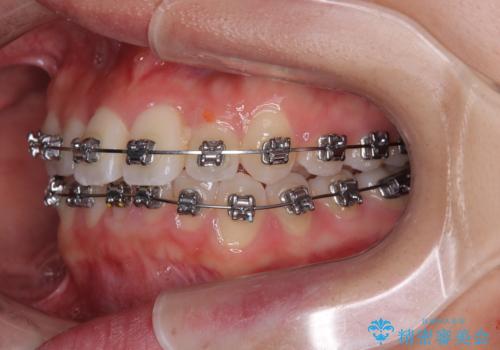

前歯のクロスバイト 裏側に隠れた歯をワイヤー装置で短期間治療

- 矯正装置

- メタルブラケット

- 上顎前歯のクロスバイトを気にして来院された患者様です。

ワイヤー矯正でもマウスピース矯正でも対応可能でしたが、マウスピースによる自己管理に一切の自信がないとのことで、ワイヤー装置にて矯正治療を行うこととしました。

装置の外見を気にしていましたが、短期間で治療を終えることができるだろうと伝えると、安価であるメタルブラケットを選択されました。

想定通り、1年強で綺麗に仕上げることができました。